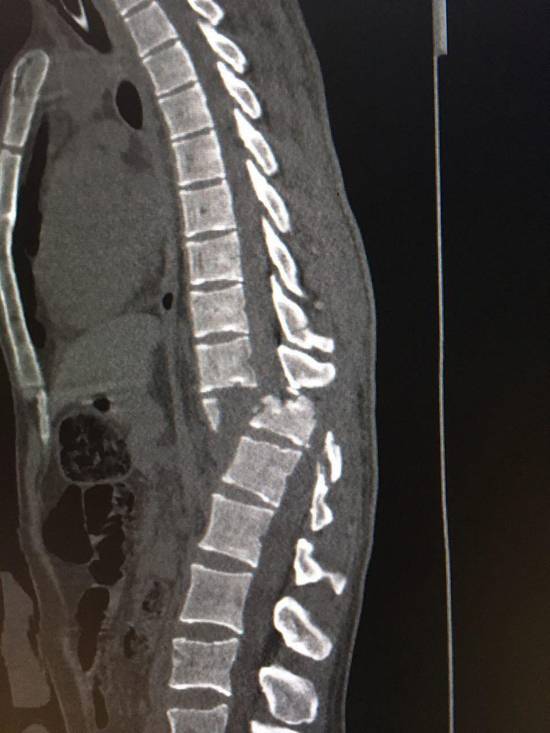

بيمار آقاى 28 ساله در تاريخ 20 آبان 96 در حين خدمت به زائرين محترم امام حسين در كربلاي معلي از ارتفاع نسبتاً زياد روي داربستهاي آهنين سقوط كرده و دچار صدمات شديد مغز و ستون فقرات شد كه عمده ضايعات آن شكستگي وسيع جمجه، كنتوزيون مغزي، كما، شكستگي و در رفتگي مهره 12 پشتي و اول كمري (L1/T12) بود. به علت گسيختگي ستون فقرات بيمار قابل انتقال به ايران نبوده و بلافاصله به بخش ICU بيمارستان امام زين العابدين در كربلا منتقل گرديد. مسئول مربوطه طي تماس با بيمارستان بهمن درخواست اعزام تيم پزشكي به كربلا را نمودند.

تيم پزشكي جناب آقاي دكتر سيد مصطفي سادات،جراح ستون فقرات، به همراه يكي از همكاران زبده خود جناب آقاي دكتر احمدرضا ريحاني و دو تكنسين ورزيده اطاق عمل در كمتر از 24 ساعت با همراه داشتن ست هاي جراحي كامل جهت تثبيت بي ثباتي ستون فقرات و بررسي وضع نخاعي بيمار به كربلا اعزام شدند. بيمار در روز پنجشنبه 25 آبان ماه در اتاق عمل بيمارستان امام زين العابدين كربلا جراحي گرديد كه حدود 4 ساعت به طول انجاميد. در حال حاضر پس از گذشت حدود يك هفته از جراحي وضع هوشياري بيمار بنا به گفته تيم معالج حاضر در كربلا رو به بهبودي مي باشد.